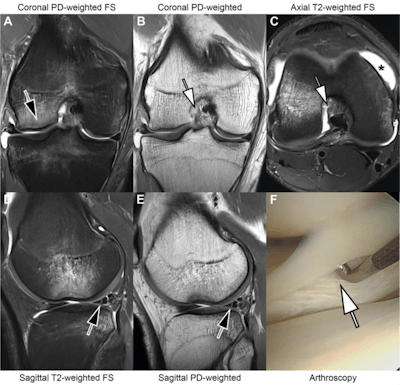

MRI scans in an 18-year-old man with right knee pain following a noncontact twisting injury playing basketball. Combined threefold parallel imaging (PIx3) and twofold simultaneous multislice (SMSx2) accelerated deep learning super-resolution turbo spin-echo sequences (A-E) were acquired at 3 tesla. Coronal proton density (PD) fat-suppressed (FS) (A), coronal PD-weighted (B), axial T2-weighted fat-suppressed (C), sagittal T2-weighted fat-suppressed (D), and sagittal PD-weighted (E) MRI scans demonstrate findings suggestive of a pivot-shift mechanism injury with a transchondral fracture of the central lateral femoral condyle (arrow in A) and transchondral bone contusion of the posterolateral tibial plateau, a femoral attachment full-thickness tear of the anterior cruciate ligament (arrows in B and C), joint effusion (asterisk in C), and a nondisplaced vertical-longitudinal tear along the posterior segment of the lateral meniscus (arrows in D and E). Readers correctly diagnosed the findings. An arthroscopic knee surgery photograph (F) demonstrates the lateral meniscus tear (arrow in F). FS = fat-suppressed. PD = proton density. Images and caption courtesy of the AJR.MRI scans in an 18-year-old man with right knee pain following a noncontact twisting injury playing basketball. Combined threefold parallel imaging (PIx3) and twofold simultaneous multislice (SMSx2) accelerated deep learning super-resolution turbo spin-echo sequences (A-E) were acquired at 3 tesla. Coronal proton density (PD) fat-suppressed (FS) (A), coronal PD-weighted (B), axial T2-weighted fat-suppressed (C), sagittal T2-weighted fat-suppressed (D), and sagittal PD-weighted (E) MRI scans demonstrate findings suggestive of a pivot-shift mechanism injury with a transchondral fracture of the central lateral femoral condyle (arrow in A) and transchondral bone contusion of the posterolateral tibial plateau, a femoral attachment full-thickness tear of the anterior cruciate ligament (arrows in B and C), joint effusion (asterisk in C), and a nondisplaced vertical-longitudinal tear along the posterior segment of the lateral meniscus (arrows in D and E). Readers correctly diagnosed the findings. An arthroscopic knee surgery photograph (F) demonstrates the lateral meniscus tear (arrow in F). FS = fat-suppressed. PD = proton density. Images and caption courtesy of the AJR.